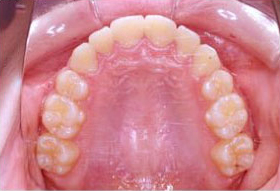

部分矯正装置の装着例

歯と歯の隙間が大きい場合は「部分矯正治療(プチ矯正)」で対応することもあります。

ラミネートべニア法と比べ治療期間はかかりますが、「歯を削らない」治療になりますので、体に優しい治療法です。前歯だけのすきっ歯が気になる場合は、部分矯正治療がおすすめです。